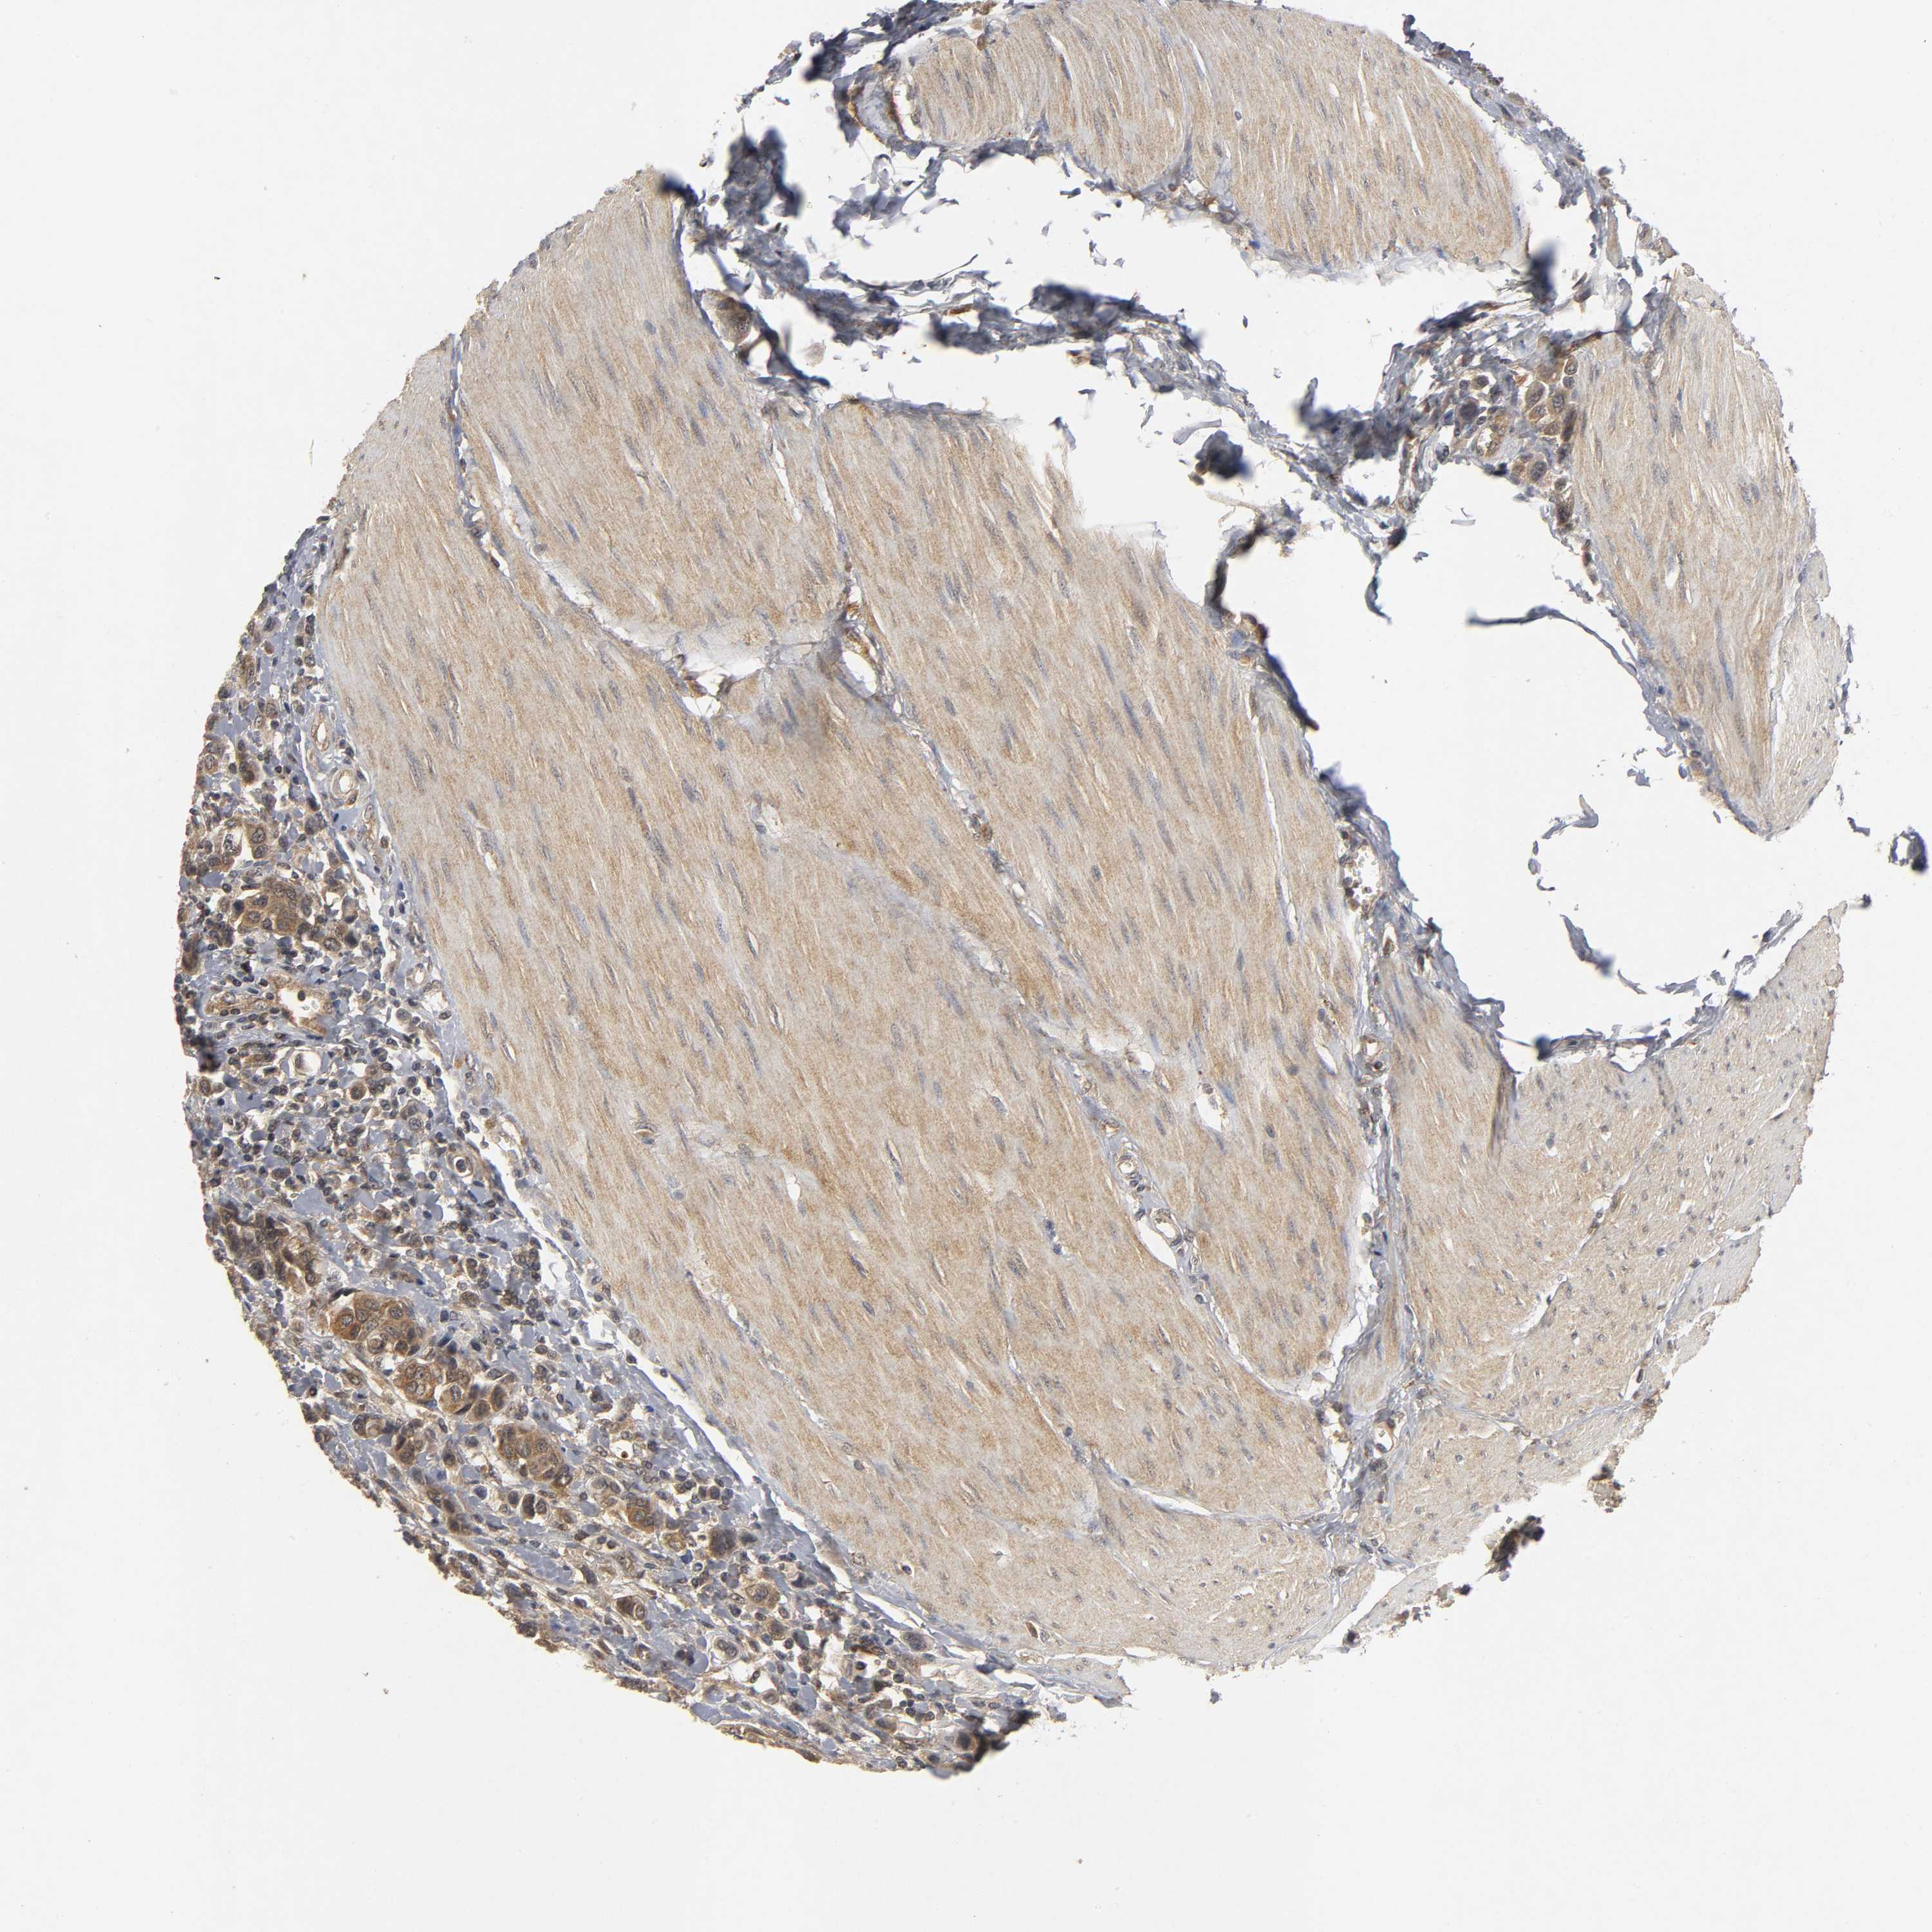

UROTHELIAL CANCER - Protein expressioni

A mouse-over function shows sample information and annotation data. Click on an image to view it in a full screen mode. Samples can be filtered based on level of antibody staining by selecting one or several of the following categories: high, medium, low and not detected. The assay and annotation is described here.

Note that samples used for immunohistochemistry by the Human Protein Atlas do not correspond to samples in the TCGA dataset.

Antibody stainingi

Antibody staining in the annotated cell types in the current human tissue is reported as not detected, low, medium, or high, based on conventional immunohistochemistry profiling in selected tissues. This score is based on the combination of the staining intensity and fraction of stained cells.

Each image is clickable and will lead to virtual microscopy that enables deeper exploration of all samples and also displays staining intensity scores, fraction scores and subcellular localization as well as patient and tissue information for each sample.

Antibody HPA019805

Antibody HPA020599

Antibody CAB004605

Staining

High

Medium

Low

Not detected

Intensity

Strong

Moderate

Weak

Negative

Quantity

>75%

75%-25%

<25%

None

Location

Nuclear

Cytoplasmic/membranous

Cytoplasmic/membranous,nuclear

Urothelial carcinoma, Low grade

Urothelial carcinoma, High grade